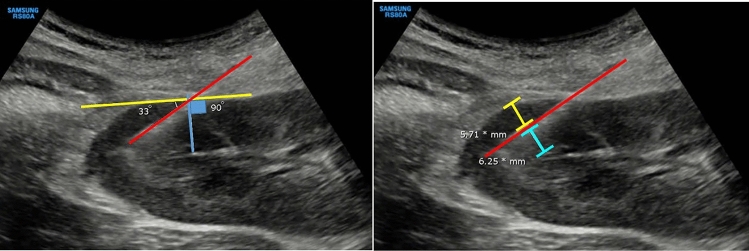

Background: Kidney biopsy is crucial for diagnosing kidney diseases but involves risks, notably bleeding, which must be balanced with diagnostic precision. This study examines the effect of the biopsy needle's cortical tangential angle and depth on specimen adequacy and safety outcomes.

Methods: This single-center, retrospective study reviewed electronic medical records from kidney biopsies performed between January 1, 2016 and December 31, 2020. Included were patients undergoing real-time ultrasound-guided percutaneous kidney biopsies. Exclusion criteria were pediatric patients, renal mass or transplant biopsies, and cases with incomplete records. Primary variables included biopsy needle cortical tangential angle and depth. Outcomes were tissue adequacy and safety, with complications assessed within 24 h.

Results: Out of 443 biopsies performed, 124 met the inclusion criteria. Our patient population had a mean BMI of 27.17 kg/m2, which met the criteria for obesity based on BMI standards for Asians, and they also had relatively small kidneys (< 9 cm) with parenchymal thinning. Biopsies at angles of 30°-60° yielded more glomeruli (12 vs. 5, p < 0.001) and had a higher pathologist-reported adequacy (82.67% vs. 59.18%, p = 0.004). Needle depth did not significantly impact adequacy. Major complications occurred in 12.90% of cases, with blood transfusions required in 8.06% and embolizations in 3.23%. All technical factors lost statistical significance after adjusting for confounders, except for increased echogenicity, which remained significant.

Conclusions: The optimal needle angle for kidney biopsies is 30°-60° for the highest diagnostic yield compared to angles < 30° or > 60°. Our study did not reveal statistically significant differences in major complications between these angle ranges. This greater understanding of the relationship between biopsy angle, needle trajectory depth, and diagnostic and safety outcomes offers valuable insights for optimizing kidney biopsy procedures.